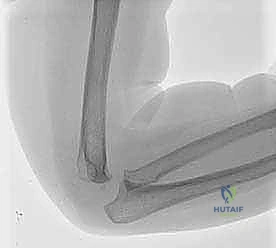

إعادة بناء عظم الفخذ البعيد بالطرف الاصطناعي: أمل جديد لمرضى أورام العظام في صنعاء مع الأستاذ الدكتور محمد هطيف

تعرف على جراحة إعادة بناء عظم الفخذ البعيد بالطرف الاصطناعي لعلاج أورام العظام. الأستاذ الدكتور محمد هطيف في صنعاء يقدم حلاً متطورًا لإنقاذ ا…